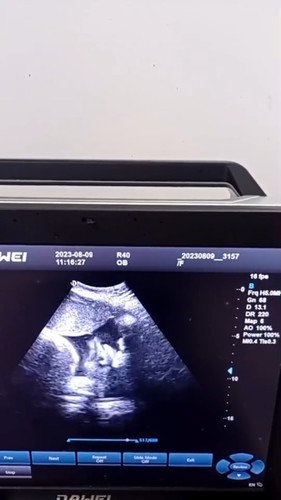

36วีค4วัน น้องนำ้นัก3300 เเบบนี้ตามเกณไมคะเเม่ๆ#ท้องแรกคะ #คุณแม่ๆช่วยแนะนำหน่อยค่ะ

VIP Parents36วีค4วัน น้องนำ้นัก3300 เเบบนี้ตามเกณไมคะเเม่ๆ#ท้องแรกคะ #คุณแม่ๆช่วยแนะนำหน่อยค่ะ